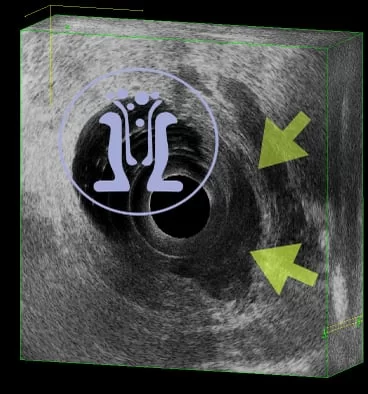

Ασθενής, 64 ετών, με ιστορικό παροχέτευσης περιεδρικού αποστήματος προ 2 εβδομάδες. Ο ασθενής ανέφερε επίσης έναρξη δυσκοιλιότητας και παρουσία αίματος στα κόπρανα από 3 μήνου. Το ενδοπρωκτικό υπερηχογράφημα έδειξε, από το δέρμα μέχρι τα στα 5-46 mm πάνω από το άνω όριο των σφιγκτήρων, διηθητική χωροκατακτητική εξεργασία πάχους 21 mm. Επιπροσθέτως, αυτή επεκτείνεται σαφώς στο περιορθικό λίπος και στο επίπεδο του πρωκτού διηθεί τον έξω σφιγκτήρα. Κάτω και στην 1η ώρα του πρωκτού ανευρέθηκε παροχετευμένο περιεδρικό απόστημα στο υπόβαθρο της διηθητικής επεξεργασίας. Συνεστήθη λήψη βιοψιών της εξεργασίας και κατόπιν ογκολογική συνεκτίμηση προ του χειρουργείου.